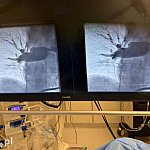

Pierwszą w historii trombektomię płucną wykonali lekarze Wojewódzkiego Szpitala Specjalistycznego w Legnicy u 75-letniego pacjenta, który trafił do SOR w ciężkim stanie po utracie przytomności i z urazem nogi. W trakcie diagnostyki rozpoznano u niego masywną zatorowość płucną, czyli stan bezpośrednio zagrażający życiu, dlatego lekarze podjęli decyzję o natychmiastowym zabiegu z użyciem nowoczesnego systemu Penumbra.

Masywna zatorowość płucna to stan bezpośrednio zagrażający życiu, wymagający natychmiastowych i zdecydowanych działań. W tym przypadku, wobec nieskuteczności leczenia zachowawczego, zdecydowaliśmy się na wykonanie trombektomii płucnej z wykorzystaniem systemu Penumbra. To małoinwazyjna metoda, która pozwala na szybkie usunięcie materiału zatorowego i natychmiastową poprawę parametrów krążeniowo-oddechowych – mówi dr hab. n. med. Piotr Rola, profesor Politechniki Wrocławskiej, kierownik Kliniki Kardiologii.